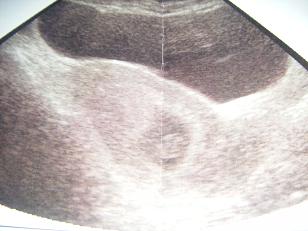

A lombik miatt kell ilyen sűrűn uhuznod?